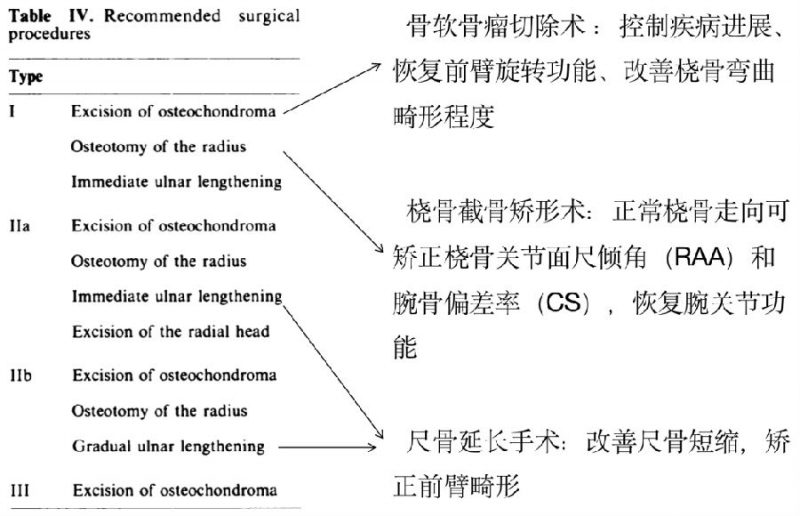

手术的类型主要包括骨软骨瘤切除术、桡骨截骨矫形术、尺骨延长等,并以不同的组合方案适用于对应的Masada分型(图4)。

图4. Masada推荐手术方案